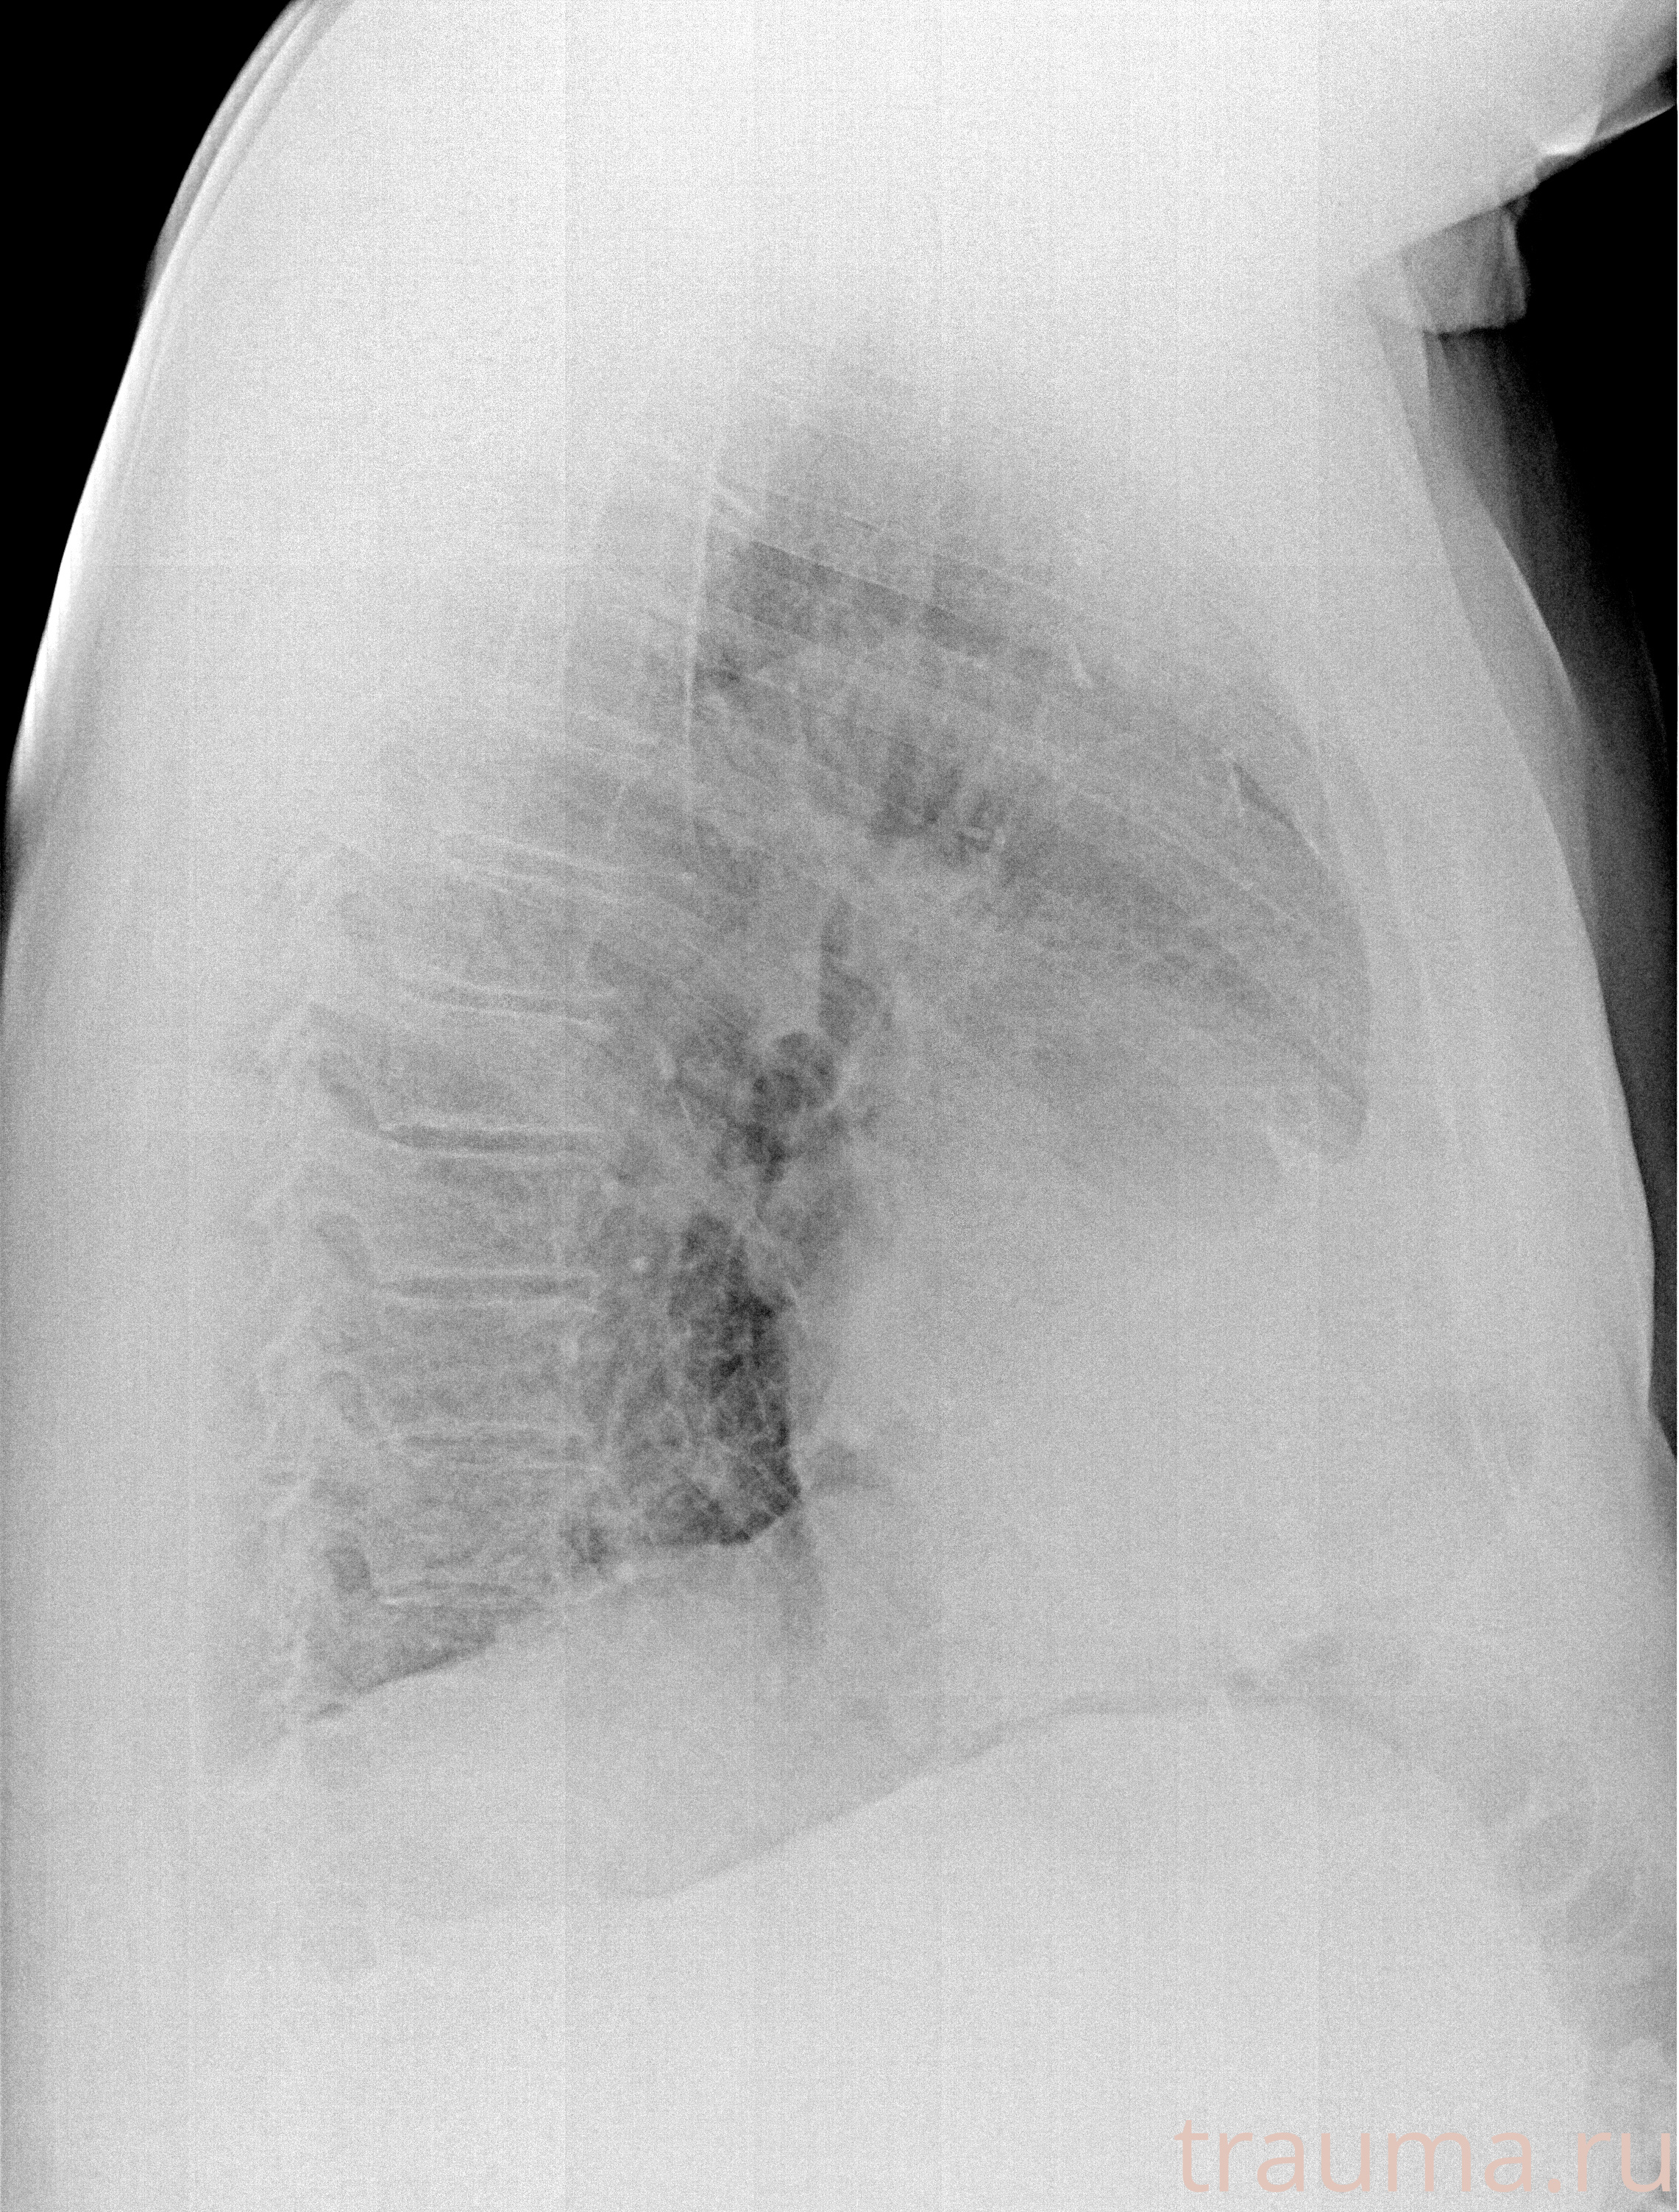

Рентген на дому: по вашему адресу приезжает врач-рентгенолог, травматолог-ортопед с мобильным рентгеновским аппаратом, проводит диагностику травмы или заболевания, делает необходимые рентгенограммы, дает рекомендации по дальнейшему лечению. Получить качественные снимки в домашних условиях возможно благодаря уникальной методике, разработанной МосРентген Центром для института  Склифосовского